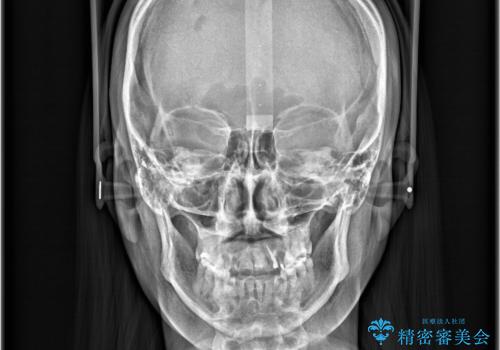

- 治療計画

- 「歯のでこぼこを治したい」を主訴に来院された患者様です。 上下ともに、歯のでこぼこが強く、上下左右4の抜歯をし、ワイヤー矯正で治療を行いました。

かなり綺麗に並ぶ事ができ大変満足していただけました。

叢生量がかなり多かったのですが、歯肉退縮も失活歯も無くとても綺麗な歯並びになりました。